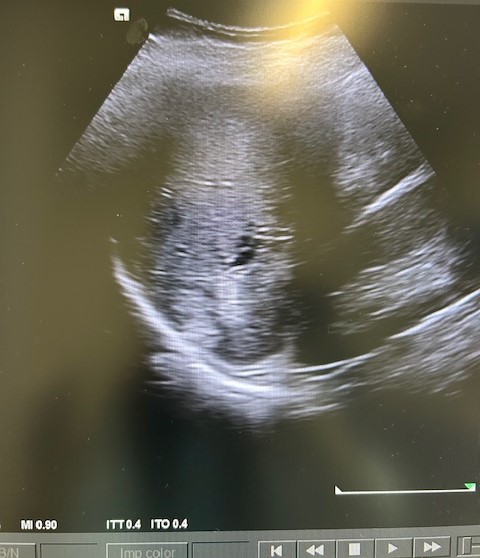

En la ecografía podemos apreciar hepatomegalia > 16 cm con múltiples imágenes en su interior hiperecogénicas sugestivas de LOE. No otros hallazgos a destacar.

El paciente fue valorado en Consultas Externas confirmando el diagnóstico. Se realiza ecografía abdominal con hallazgos de múltiples nódulos hepáticos de entre 12-35mm. En la colonoscopia, neoplasia circunferencial con aumento de consistencia, áreas ulceradas y necrosis, con estenosis incompleta, siendo compatible con adenocarcinoma de sigma.